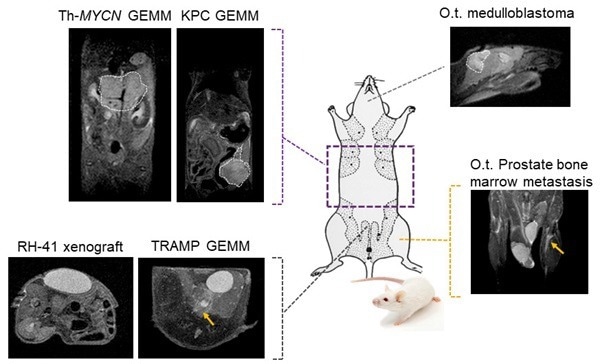

Tumor visualization in various cancer models: Fat-suppressed T2-weighted imaging can be used to detect and quantitatively characterize the growth of a wide range of cancer models. Image Credit: Scintica Instrumentation Inc

Fat-suppressed T2-weighted imaging can be used to detect and quantitatively characterize the growth of a wide range of cancer models. Image Credit: Scintica Instrumentation Inc